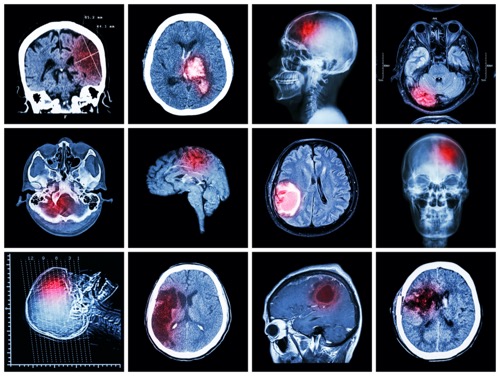

大约1/3的原发性脑肿瘤是脑膜瘤。它们通常是良性的,生长缓慢。脑膜瘤从覆盖大脑和脊髓的组织中生长出来,并对这些区域造成压力。脑膜瘤在儿童中很少见,在 60 岁以上的妇女中较常见。脑膜瘤的症状包括:头痛、手臂或腿力量虚弱、癫痫发作、人格改变和视力问题。

脑膜瘤可生长在大脑内多个部位,不同位置的脑膜瘤症状各异,相应的手术切除方案和手术入路都各有不同。认清脑膜瘤的好发部位,有助于医生根据对应位置的肿瘤制定出个性化的手术切除方案。